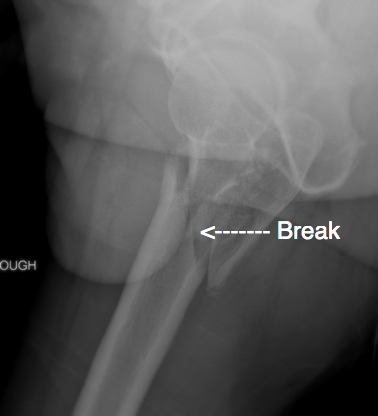

leg break

The break at the top of the fright femur.

In early April, one month after the Argus, I went out one Saturday morning to ride the Raithby trails. About 300m from the gate to my estate, still on the main road, I turned my head to check the traffic behind, and the next I knew I was lying in the road in a great deal of pain. Fortunately, my MTB friends were right behind me and were able to summon an ambulance. It turns out I had shattered my upper femur, and I was quickly taken to hospital - again! The next day I was operated on and titanium rods and pins were inserted into my femur and hip. It was a very painful ordeal.